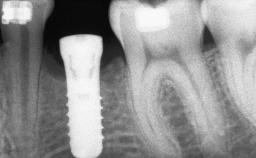

# of Teeth 1

# of Implants 1

Type of Implants Two-Piece

Bone Augmentation Staged|Vertical